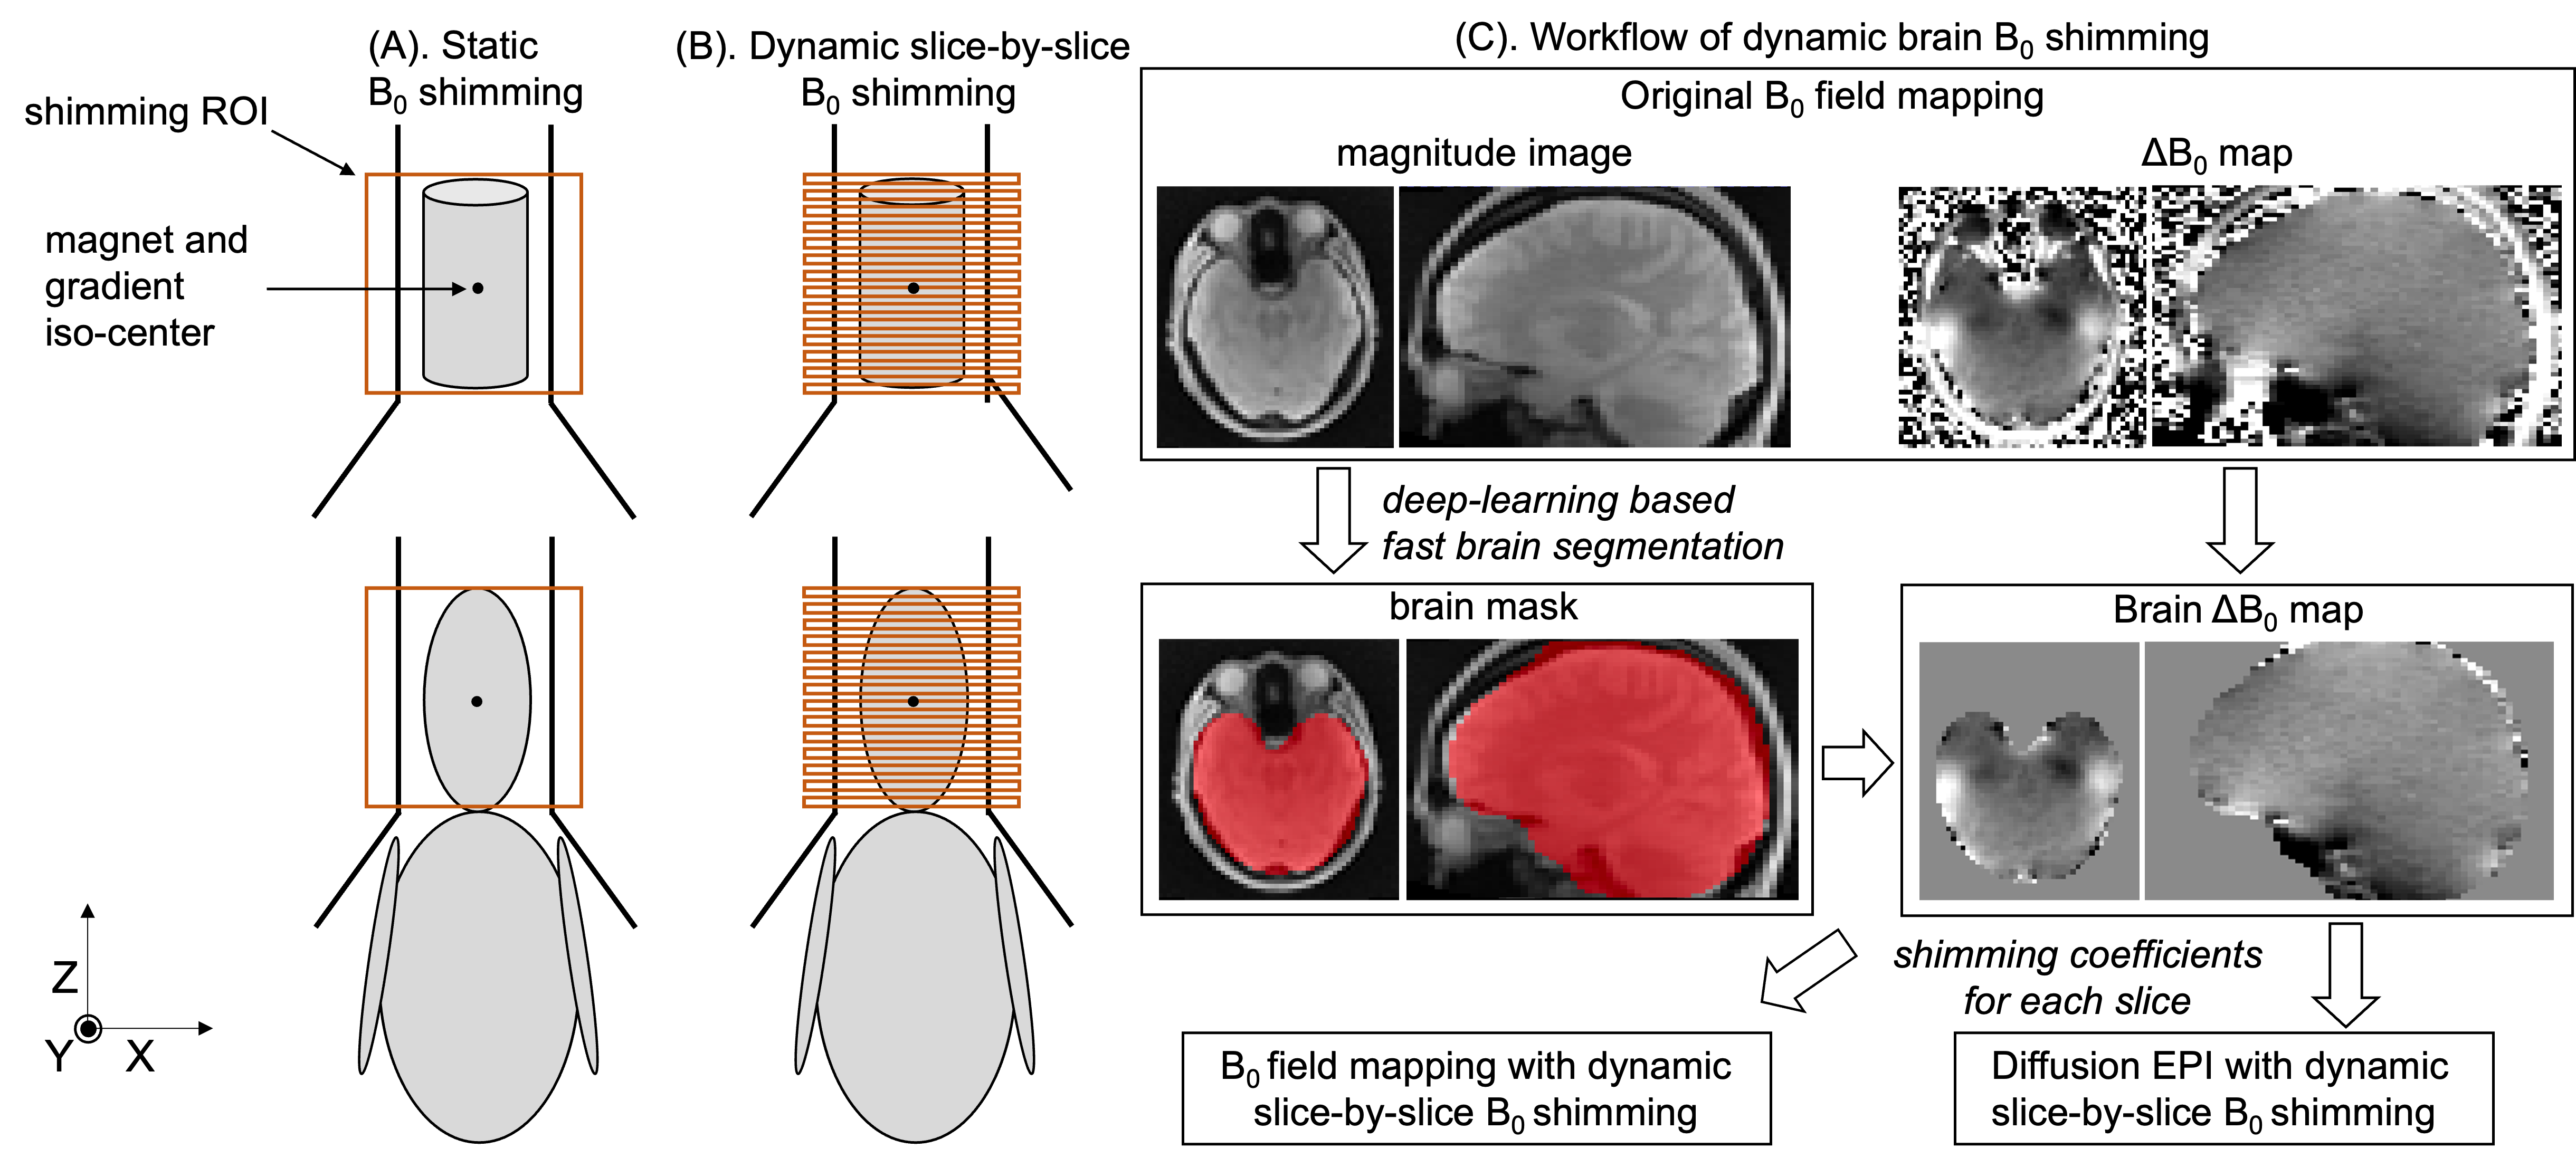

6.2 Fast brain segmentation to determine the shimming area

shimming in brain tissues has been shown to effectively reduce local image distortion in brain tissues, compared to shimming in the whole head regions which include skulls and other non-brain tissues. 30 Deep-learning-based brain extraction 32 can significantly reduce the computation time, enabling in-scanner implementation of automated and personalized shimming ROI. In this work, a customized deep-learning-based brain segmentation tool 32 was applied to segment brain tissue from the magnitude image of field mapping (Figure 1).

The segmentation and computation of shimming coefficients were implemented in the scanner. The processing pipeline was fully automated and took less than 10 seconds.

For each scan session, a first axial field map (i.e., ’Original ’) covering the whole phantom or the whole brain (Figure 1A) was measured with 2D multi-echo spoiled gradient echo acquisition. Two sets of shimming coefficients were calculated from the acquired field map, i.e., (1) dynamic 2D slice-by-slice shimming assuming linear gradient fields and (2) dynamic 2D slice-by-slice shimming using actual gradient fields. The actual gradient field of each voxel was approximated by using the order spherical harmonics.28 Another two field maps (i.e., ’Measured post-shim , linear’ and ’Measured post-shim , actual’) were measured by applying the shimming coefficients for each slice in field mapping using a modified 2D multi-echo spoiled gradient echo sequence with dynamic slice-by-slice shimming. Same imaging parameters were applied for all the field shimming, as shown in Table 1.